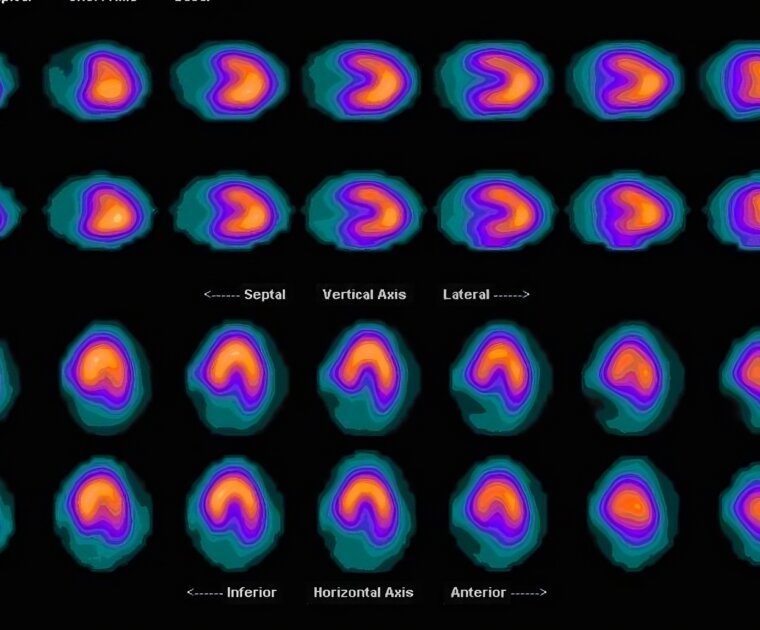

In this report, Eva-Nour Repussard discusses the findings of a 2022 multistakeholder roundtable jointly convened by BASIC, the University of Bristol, Imperial College London, The Open University and Rolls-Royce, on nuclear medicine technologies.